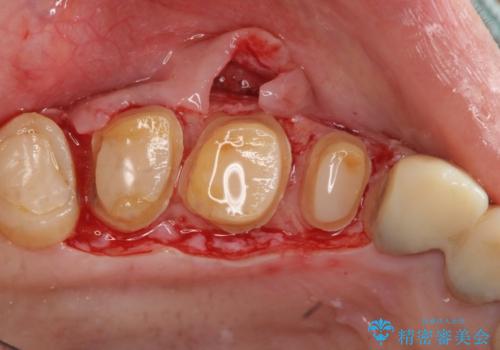

- 重度の歯ぎしり癖で歯がすり減り、見た目・噛み合わせの改善とこれ以上すり減る前の処置を希望され来院されました。

高さが短くなってしまった歯は、安定したクラウンを作るのが難しいため歯ぐきを下げる歯周外科を行ったのちに強度に優れるフルジルコニアクラウンで補綴治療を行います。

すり減ってしまった歯に対し、歯冠長延長術(歯周外科)を行うことで安定したクラウンを製作・装着することが出来ました。